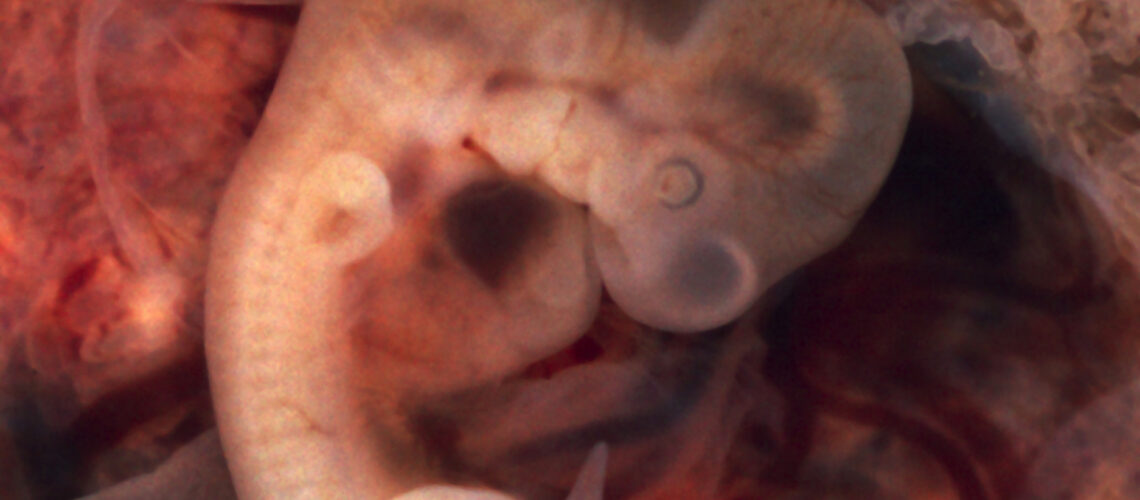

L’Assemblea nazionale francese ha adottato una legge sulla bioetica radicale a che entrerà probabilmente in vigore all’inizio di luglio, una volta superati gli ultimi ostacoli legislativi dopo il terzo passaggio. La nuova legge segna la fine del riconoscimento della paternità, ma anche l’inizio delle chimere (ossia di esseri ibridi, dotati di … Leggi tutto Ingegneria genetica e chimere, la nuova legge bioetica francese